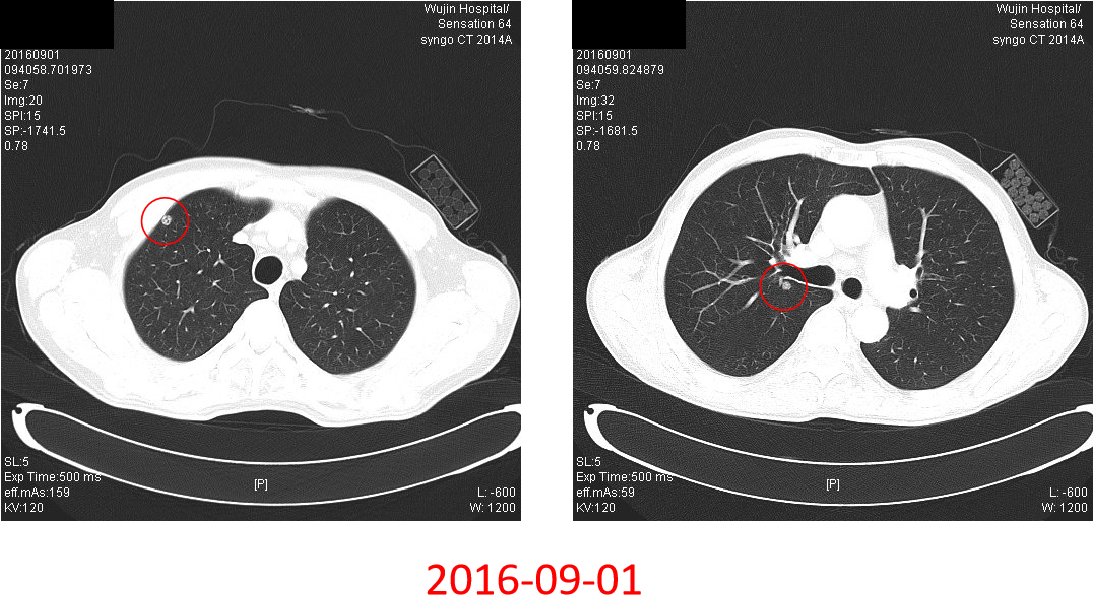

2016-09-01:

诊断:升结肠癌IV期(双肺多发转移)

评估:晚期结肠癌,初始不可切除